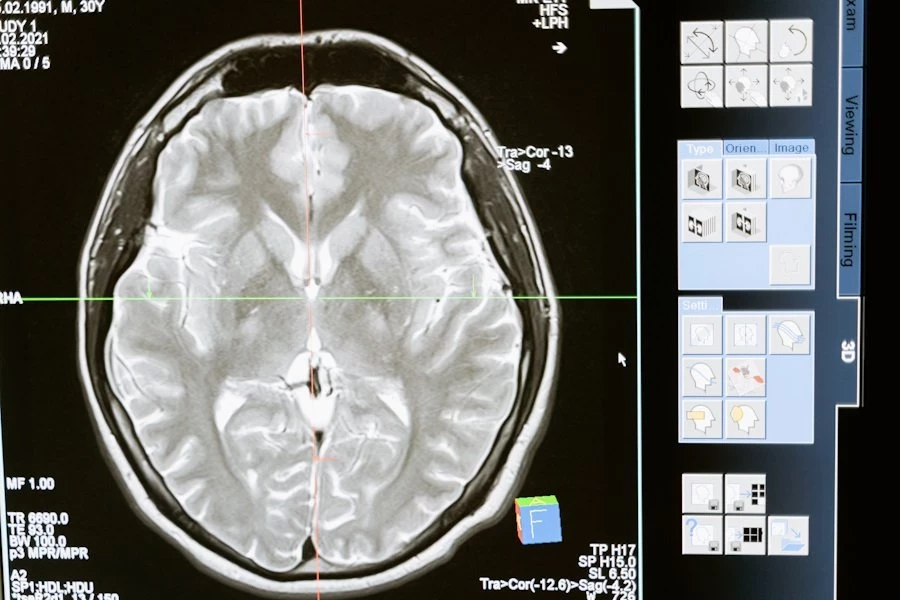

Ученые из Калифорнийского университета в Беркли проводят исследования двух частей мозга, которые отвечают за принятие решений: передней поясной коры (ACC) и орбитофронтальной коры (OFC), чтобы понять их роль в этом процессе, сообщает Nature Neuroscience.